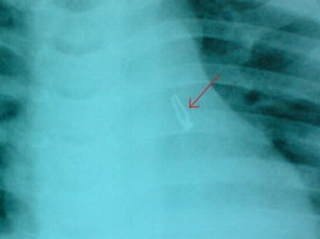

Gia đình cháu A. cho biết, cháu bị ho nhiều gia đình cho cháu uống thuốc có giảm nhưng sau đó lại bị tái lại. Cứ hết thuốc gia đình lại cho cháu đi khám và mua thuốc, rồi nhập vịện tiêm thuốc tại địa phương nhưng không khỏi nên đã đưa đến bệnh viện Nhi đồng 1. Tại bệnh viện, các bác sĩ thấy cháu có những dấu hiệu nghi viêm phổi và cho chụp phim X quang phổi.

Kết quả là tình trạng phổi bị viêm ở cả 2 bên, bên phổi trái còn bị xẹp một phần. Chụp phim kiểm tra lại giúp xác định được có hình ảnh vật kim khí trong lồng ngực bên trái.

Nội soi đường thở thì thấy có nhiều mủ đục ở cuống phổi bên trái. Ở giữa ổ mủ gắp ra được một bóng đèn điện nhỏ, lọai đèn trang trí làm đẹp nhà cửa.